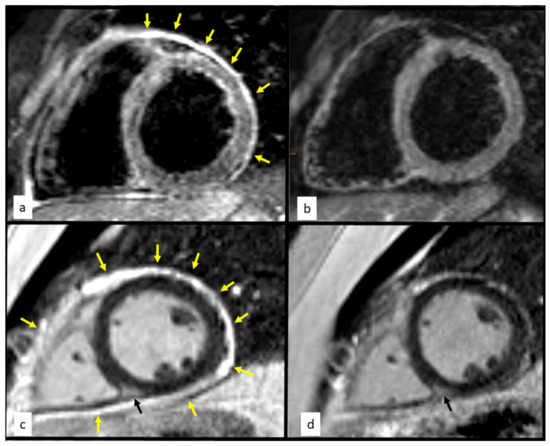

Chest Pain of Atypical Cause in a Young Man

Granulomatosis with polyangiitis (GPA) is a rare systemic vasculitis that classically affects the upper respiratory tract, lungs, and kidneys. The involvement of other organs occurs but is less frequent. Clinically overt cardiac involvement is rare. We present a rare case of thoracic pain [...] Read more.

Granulomatosis with polyangiitis (GPA) is a rare systemic vasculitis that classically affects the upper respiratory tract, lungs, and kidneys. The involvement of other organs occurs but is less frequent. Clinically overt cardiac involvement is rare. We present a rare case of thoracic pain caused by cardiac involvement in GPA, without any other symptoms. The diagnosis was made using an integral approach, with several complementary imaging modalities, including cardiac histology. Full article